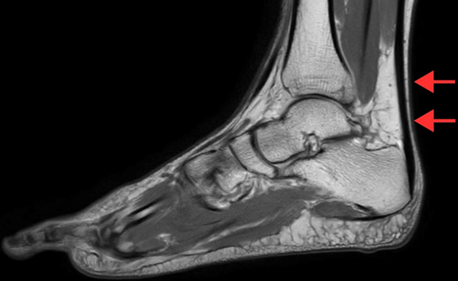

A rare case of Kager´s fat pad syndrome with retrocalcaneal bursitis following ankle sprain

The Kager´s fat pad is an adipose structure located between the Achilles tendon, calcaneus, and flexor hallucis longus. Kager´s fat pad syndrome results from overuse, trauma, and underlying conditions like tendonitis. Pain and inflammation at the posterior side of the ankle are the primary complaints of patients with Kager´s fat pad syndrome. A 34-year-old male monk presented with posterior ankle pain, localized swelling, and reduced range of motion (ROM) that developed over several weeks. He had a history of barefoot walking and an ankle sprain sustained while climbing stairs two months earlier. Clinical examination revealed posterior ankle tenderness and dorsiflexion limitation. Magnetic resonance imaging (MRI) was ordered to confirm suspicions of ligamentous or soft tissue injury. Imaging demonstrated edema of Kager´s fat pad, sprain of the anterior and posterior talofibular ligaments, sprain of the calcaneofibular ligament, and retrocalcaneal bursitis. Kager´s fat pad pathology is a recognized but underdiagnosed source of posterior ankle pain, often seen in conjunction with other mechanical stressors. Imaging findings guided a conservative treatment plan consisting of cryotherapy, shockwave therapy, Maitland mobilization, taping, myofascial release, range of motion exercises, and strengthening exercises. The patient showed marked improvements in pain and ankle function over four weeks. This case supports prior findings that musculoskeletal imaging significantly enhances physiotherapy treatment planning.